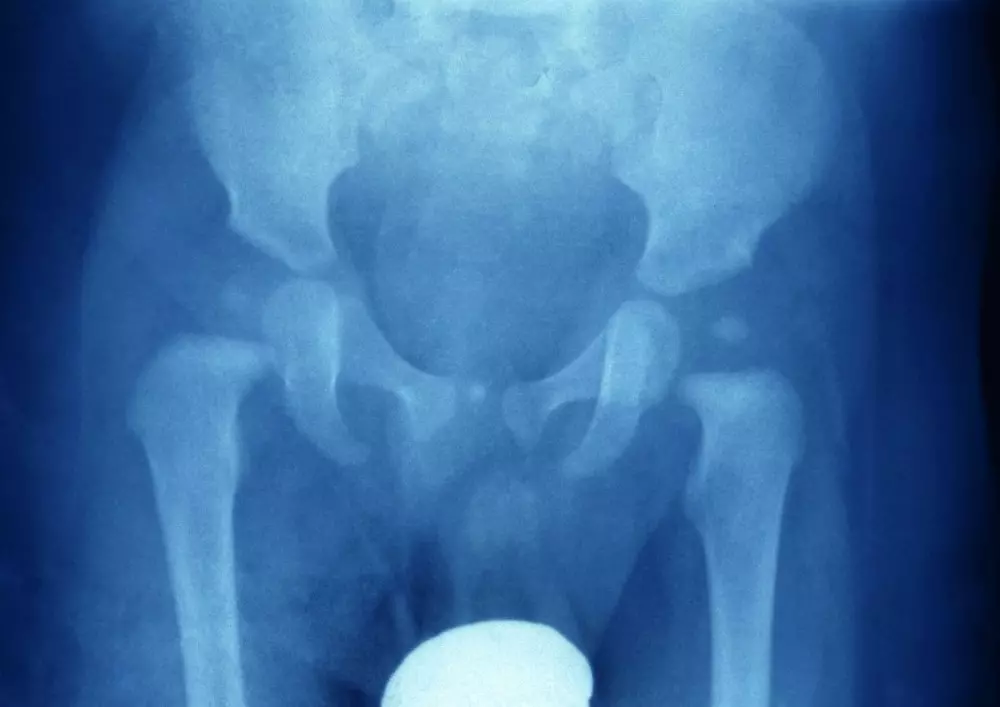

Dysplazja stawu biodrowego

Zachęcamy także do lektury artykułu, w którym omówiony został problem, jakim jest dysplazja stawów biodrowych u dzieci oraz innowacyjna metoda leczenia, czyli FirstBIKE. Dysplazja stawu biodrowego dotyka aż 5% populacji noworodków i określana jest jako choroba uwarunkowana genetycznie. Wiąże się ona z niedorozwojem panewki stawowej i słabym rozwojem pozostałych struktur okołostawowych. W tekście przedstawiamy objawy towarzyszące dysplazji stawu biodrowego oraz nieinwazyjne metody leczenia. Autor dodaje, że FirstBIKE powinien towarzyszyć tym metodom, ponieważ wspomaga prawidłowe ułożenie bioder i ich ćwiczenie w trakcie rozwoju.